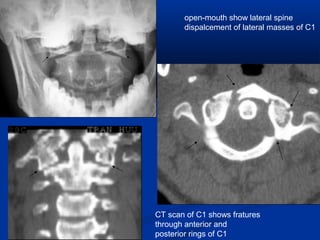

AP open mouth

If the lateral margin of the atlas lateral mass lies

lateral to the lateral axis margin, this may be a

radiologic sign of Jefferson’s fracture, odontoid

fracture, alar ligament instability, or rotatory

atlantoaxial subluxation

open-mouth show lateral spine

dispalcement of lateral masses of C1

CT scan of C1 shows fratures

through anterior and

posterior rings of C1